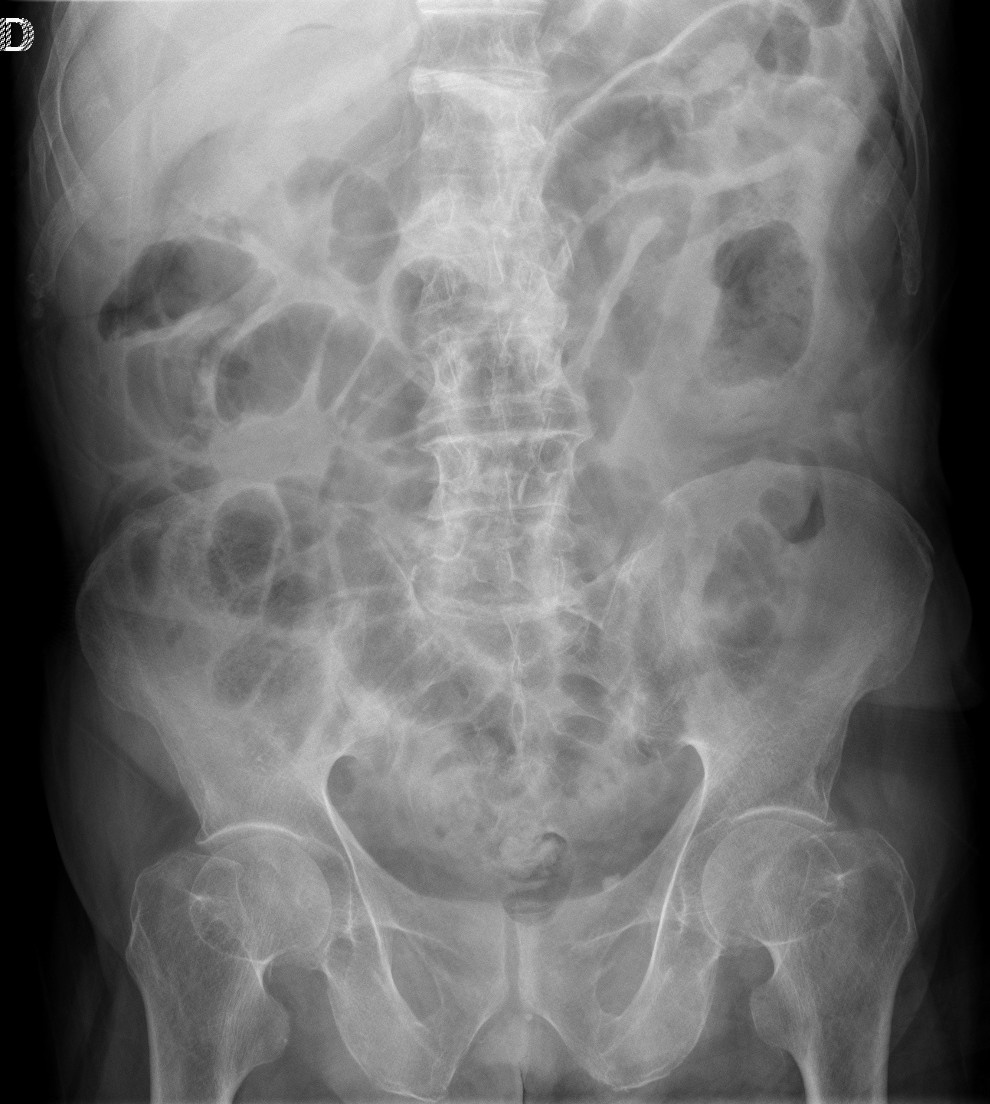

Paciente que acude a urgencias por tos febrícula. Se realiza placa simple PA de tórax, se observa lo siguiente:

Un paciente sin síntomas abdominales en el que casualmente hemos visto el signo de chilaiditis.